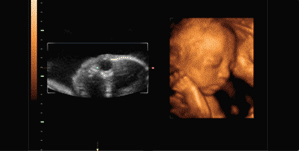

四维彩超是目前世界上先进的彩色超声设备,是在三维超声图像的基础上加上时间维度参数,从而更直观更清晰地呈现胎儿在宫内的动态图像,所以,有时也被称作实时三维。

通俗地说,三维彩超是单张图片,四维彩超近乎录像,其两者画面都是黑白色或黄土色,只不过四维彩超可以让孕妈妈看到胎宝宝一连串的动作,这让不懂超声医学的孕妈妈感到亲切、直观。

四维彩超能够多方位、多角度地观察胎宝宝在宫内的实际生长发育情况,为早期诊断胎儿先天性体表畸形和先天性心脏病等提供科学依据。

四维彩超不仅仅是感觉胎宝宝的呼吸和运动,而是可以亲眼目睹他们的一举一动和乖巧的秀容。

更为重要的是,四维彩超能够多方位、多角度地观察宫内胎儿的生长发育情况,为早期诊断胎儿先天性体表畸形和先天性心脏疾病提供准确的科学依据。